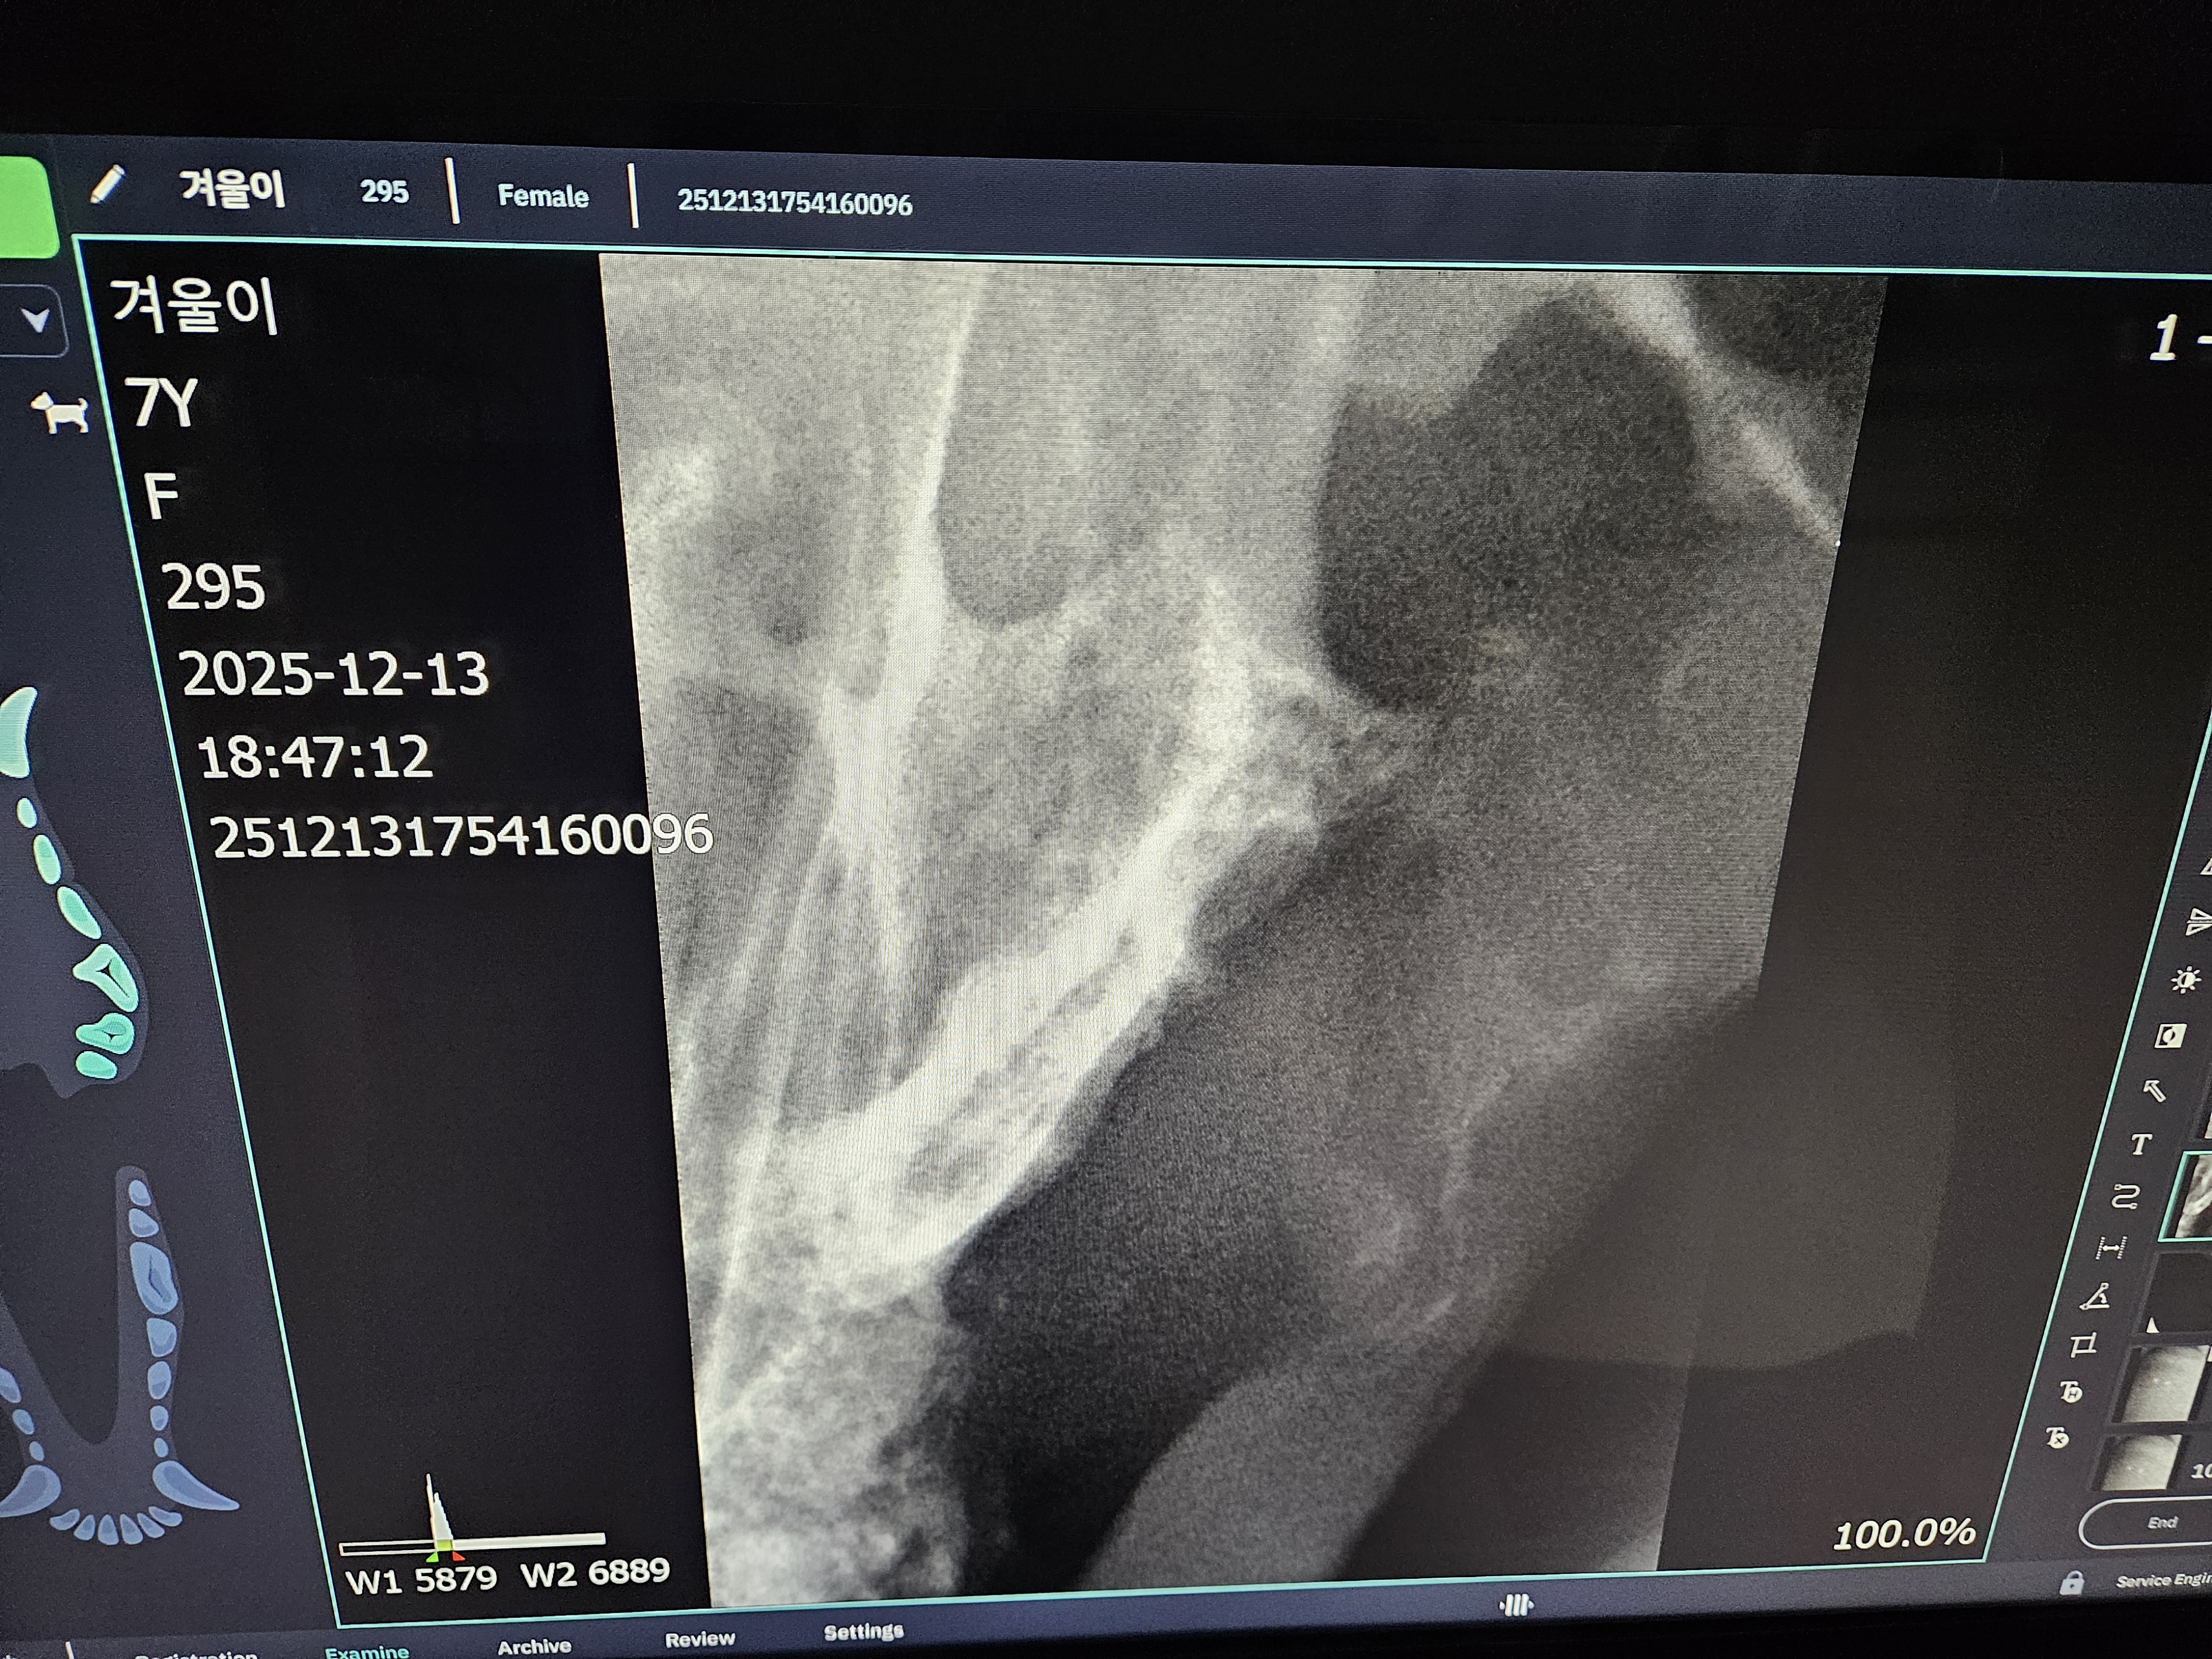

*치아 엑스레이 사진 입니다.

| 치료과정 | 겨울이 염증 수치가 엄청 높았습니다. 보통 정상 수치가 5까지인데 109정도로 엄청 높게 나왔다고 합니다. 염증 수치 같은 경우는 단점이 어떤 부위에 문제가 있는지를 나타내는 수치는 아님. 그런데 겨울이는 구강 안쪽이 엄청 빨개졌었음. 그래서 구내염에 의한 급성염증 수치라고 생각하면 되고, 마취 전에 한 검사는 간수치랑 신장 수치를 체크해주셨는데 콩팥이나 다른 부위는 기능이 정상이라고 하셨습니다. 겨울이 같은 경우는 밥을 잘 못먹었을 뿐이지 간수치나 신장 수치는 특이사항이 없다고 하셨습니다. 겨울이가 입원한 날 빈혈이 너무 심해가지고 수액을 맞았습니다. 그런데 적혈구 개체수도 부족해서 계속 수액을 맞을 수가 없었습니다. 혈액의 적혈구가 부족한혈액이 점점 많아지는 거예요. 항생제 수액으로 마무리 했다고 하셨고,급성 염증 수치는 시간이 지남에 따라서 무조건 좋아진다고 하셨는데, 약은 항생제와 염증 가라앉히는 소염제를 처방해준다고 하셨습니다. 치아 엑스레이 찍은 결과 치조골이라고 해서 이빨에 잡고 있는 뿌리가 어 다 녹아 있었고,그래서 이런 부분들이 이빨의 기능을 상실한 채로 그냥 이가욱씬욱씬한 상태로 있었을거고, 그래서 이빨을 뽑아야 하는 상태라고 하셨습니다. 송곳니는 부러져 있는 부위도 있어서 그런 이빨들은 뿌리 안남기고, 제거를 하셨다고 했습니다. 이빨 자체가 약한 상태이고 전체적으로 발치를 다 한 상태라고 하셨습니다. |